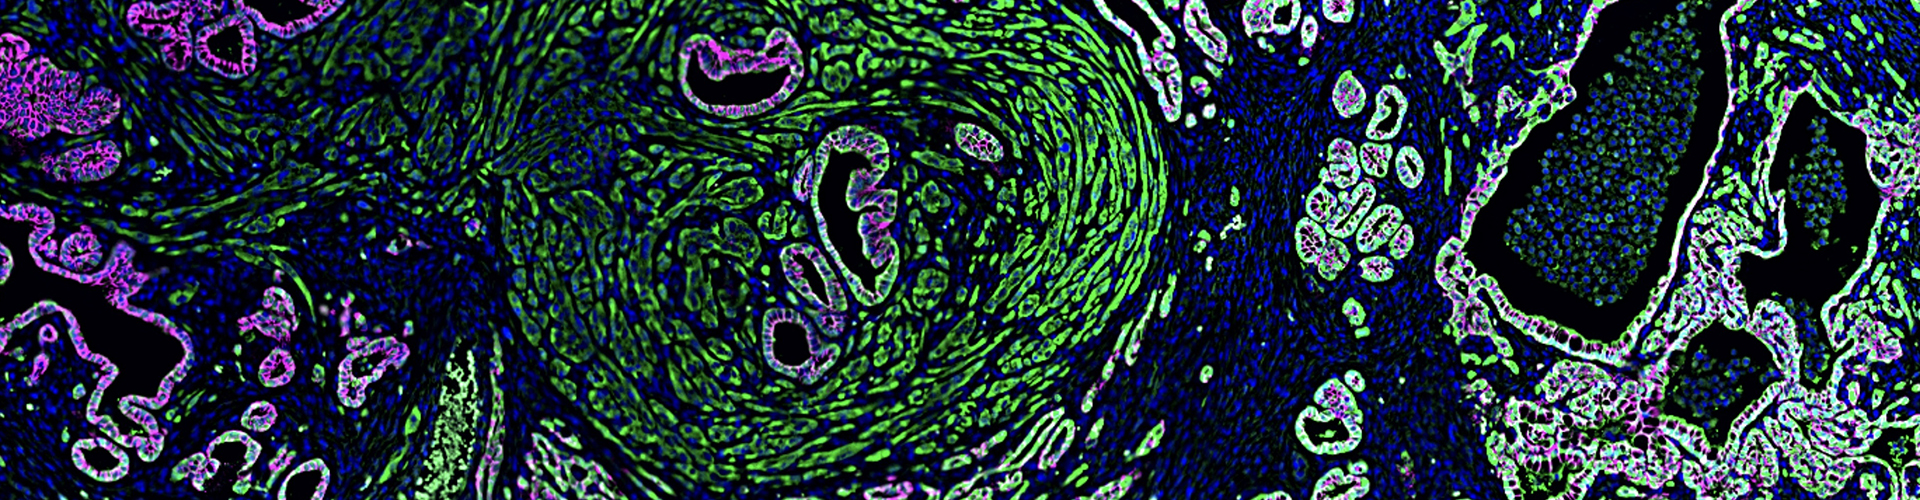

• Understanding mechanisms of cellular plasticity that facilitate metastasis

• Mechanism of epithelial-to-mesenchymal transition (EMT)

• Building novel genetically engineered mouse models to study epithelial plasticity and squamous/basal/quasimesenchymal subtypes in pancreatic cancer progression

cellular plasticity